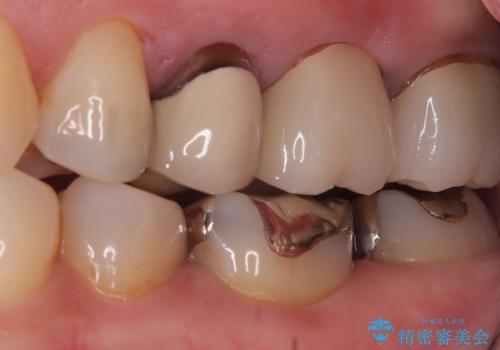

唇側マージン不適なこと説明し、審美性・適合性に優れたセラミッククラウン(スタンダード)でのやり替えとなりました。

治療途中、一度仮歯に置き換えを行っています。